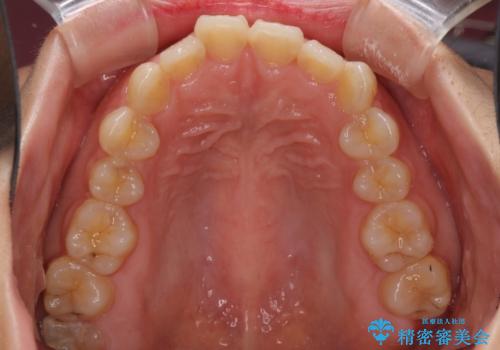

- 前歯のデコボコを治したいとのことで来院された患者様です。

上下顎ともに歯列全体の側方拡大とIPR(歯と歯の間を削る)によってデコボコが解消するように設計し、インビザラインにより治療を行うこととしました。

後方移動に際し、残っていた上顎の親知らずを抜歯することとしました。